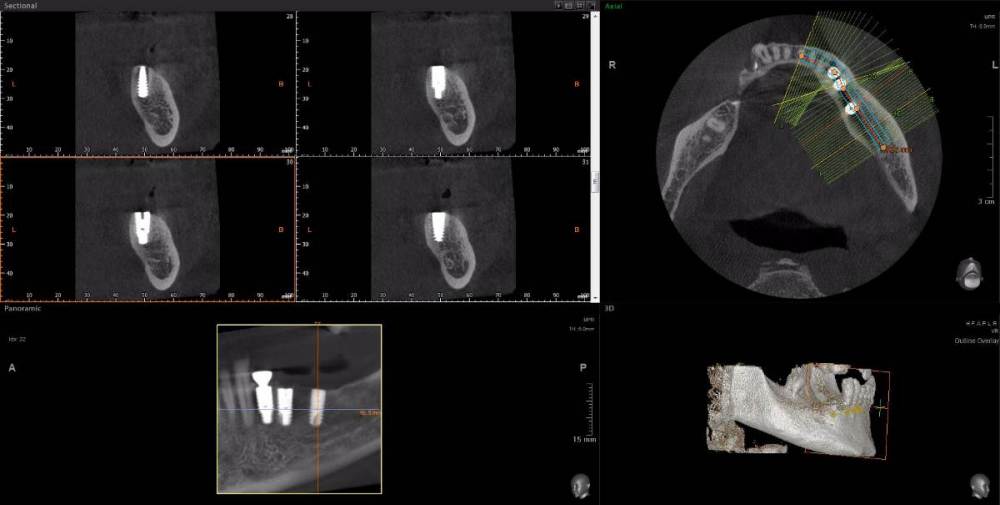

m-art-a23 Опубликовано 21 апреля, 2021 Поделиться Опубликовано 21 апреля, 2021 Здравствуйте. Два дня назад мужу установили 5 имплантов Ankylos на нижнюю челюсть (2+3). Спустя 30-40 мин после операции появилась сильная острая боль, которая не уменьшается по настоящее время. Боль похожа по ощущениям на пульпитную, не снимается никакими НПВС, кроме кеторолака. А/б, А/гистаминные, холод местно, хлоргексидин - все рекомендации выполнялись. На осмотре врачом не обнаружено следов воспаления, КТ сделал - без особенностей. Что может служить причиной такой боли, сколько она может длиться и что делать в данной ситуации? Врач-имплантолог ничего внятного не предложил. Ссылка на КТhttps://cloud.mail.ru/public/EvKn/ULqxLy6BD Ссылка на комментарий

red_butler Опубликовано 22 апреля, 2021 Поделиться Опубликовано 22 апреля, 2021 7 минут назад, m-art-a23 сказал: Нет, не один. Но он лучший. Скажите пожалуйста, что служит причиной боли, по-Вашему? Неужели все импланты нужно убирать только по Кт трудно судить, но есть вопросы по позиционированию имплантов... боль может быть вызвана перегревом кости во время формирования ложа импланта, но в этом случае она появляется примерно с третьего дня. Так же боль может вызывать гиперкомпрессия импланта, и может болеть кость если ее придавили формирователем десны. Я бы обсудил с хирургом удаление среднего импланта слева 1 Ссылка на комментарий

Irouil Опубликовано 22 апреля, 2021 Поделиться Опубликовано 22 апреля, 2021 Я бы рекомендовал удаление среднего импланта слева, независимо от наличия/отсутствия болевых ощущений боль может быть признаком каких-то описанных моим коллегой процессов, а может ничего кроме самой боли не означать (менее вероятно, но и такое бывает). Если удаление упомянутого импланта поможет против болевого синдрома - это win-win если хирург не видит необходимости удаления импланта, я бы рекомендовал сходить на осмотр к ортопеду, который будет в будущем эти импланты протезировать. Возможно у него найдутся весомые аргументы для коллеги 3 Ссылка на комментарий

Irouil Опубликовано 22 апреля, 2021 Поделиться Опубликовано 22 апреля, 2021 (изменено) 1 час назад, m-art-a23 сказал: Благогдарю за совет. Если Вам не трудно, объясните пожалуйста, что не так со средним имплантом. Описанные процессы, если таковые имеют место быть, должны постепенно прийти в норму? Другими словами, сколько еще нужно времени, чтобы окончательно принять решение об удалении импланта (имплантов)? Сегодня третьи сутки после установки. Боль сохраняется. Средний имплант расположен чрезвычайно близко к соседнему, расположенному кпереди от него. С очень большой долей вероятности это может привести к значительной резорбции (убыли) костной ткани между ними, что для любых имплантов очень вредно, а для конкретно Анкилосов - губительно из-за особенностей их протезирования. Если неблаготворные процессы (компрессионный или термический некроз) присутствуют, то импланты просто не интегрируются (не приживутся) - те, что зашиты не выдержат нагрузки при раскрытии, а тот, на котором стоит ФДМ - расшатается через 2-3 недели. Это не призыв проверять его стабильность языком, сейчас его лишний раз лучше не трогать. В норме после имплантации боли держатся 1-2 дня, если все не очень хорошо - держатся 2-3 недели, но даже в таком случае имплант может интегрироваться, поэтому решение об его удалении в таком случае должно, по моему убеждению, быть совместным между врачом и пациентом, и приниматься в индивидуальном порядке Изменено 22 апреля, 2021 пользователем Irouil Ссылка на комментарий